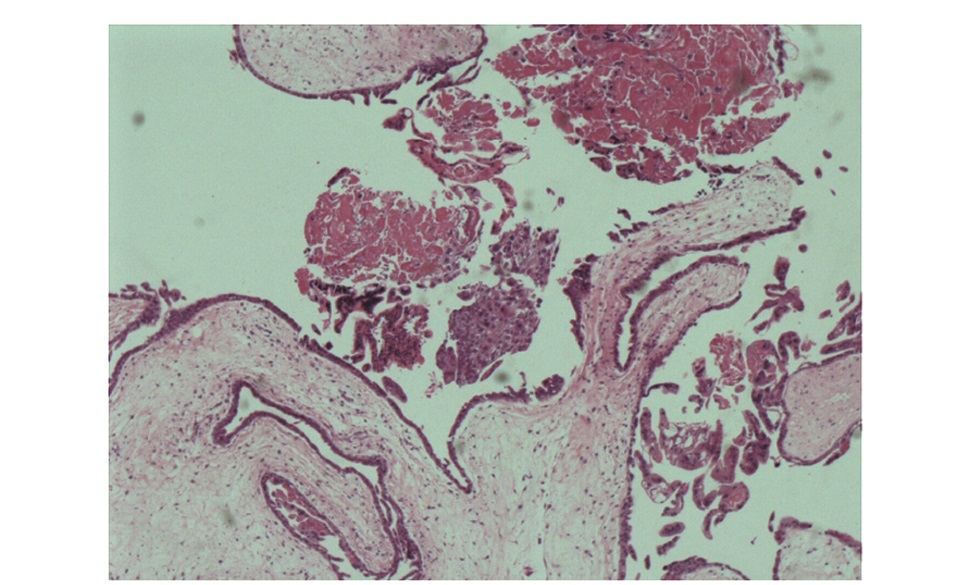

Abstract: Hydatidiform mole is a benign gestational trophoblastic disease. Twin pregnancy with hydatidi-form mole and a coexistent fetus is extremely rare. The diagnosis is usually delayed and the pregnancy is often terminated due to severe vaginal bleeding or other complications. There are few guidelines for termination methods. Here we report a case of successful labor induction and vaginal delivery of twin pregnancy with hydatidiform mole and a coexistent fetus at 16 weeks of gestation. The diagnosis, treatment principles, and termination methods are discussed.